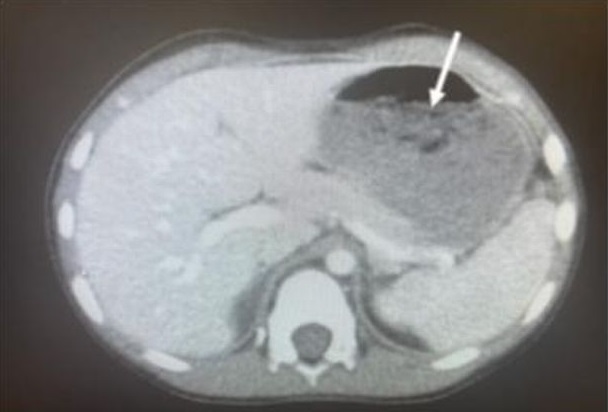

В США пятилетний ребенок попал в больницу штата Огайо с симптомами судорог и диареи. После проведения рентгеновского исследования стало ясно, что причиной проблем был гигантский комок жевательной резинки. Ребенок проглотил около 40 штук резинок, воспользовавшись моментом, когда его родители отвлеклись. Об этом сообщает Daily Star.

Согласно публикации в журнале JEM, проведенное исследование показало наличие большого количества жевательной резинки в желудке маленького пациента.

Чтобы извлечь комок, медики использовали металлическую трубку и щипцы. Процедура вызвала некоторые дискомфортные ощущения и временное заболевание горла, но по счастью, ребенок избежал серьезных последствий для здоровья.